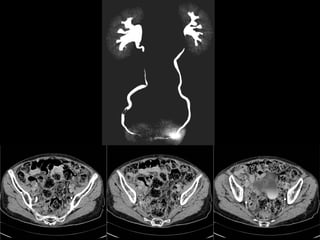

Estudio de elección:  UROTC   Fases: sin contraste con contraste: arterial, portal y eliminación que permite evaluar la hematuria con un único examen. Fase sin contraste: litiasis. Fase arterial:  alteraciones del parénquima (masas), evaluación de otros órganos abdominales Cortes finos en fase tardía:  distensión del sistema excretor y uréteres con contraste para evaluar patología uroepitelial (95% sensibilidad en detección de patología maligna del uroepitelio)  UROTC:  evalúa vejiga pero tumores planos difíciles de observar.  equivale a 4 pielografías de eliminación, > 10 mSv